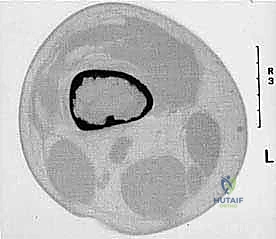

2. الموقع (Site - T): هل الورم داخل الحيز العظمي (Intracompartmental - T1) أم اخترق القشرة وخرج للحيز الخارجي (Extracompartmental - T2)؟

3. الانتشار (Metastasis - M): هل انتقل الورم لأعضاء أخرى (M0 لا يوجد، M1 يوجد انتشار)؟

بناءً على هذا التقييم الدقيق، يتم وضع خطة جراحية متكاملة لضمان استئصال الورم بالكامل دون ترك أي خلايا سرطانية.